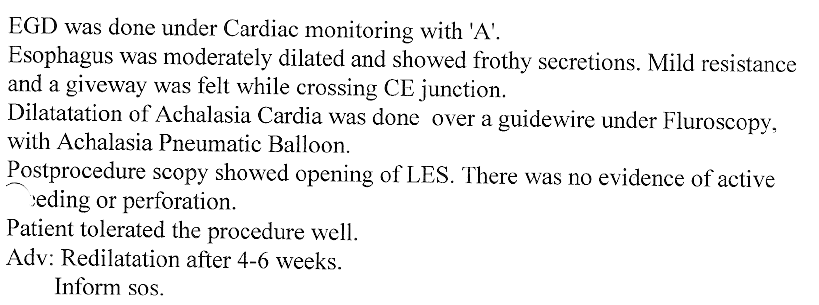

Strong contractions of the food pipe is known as dysmotility of esophagus and an unusual condition known

as Achalasia Cardia due to powerful contraction of the valve of the esophagus at its lower end which

can cause difficulty in swallowing.

Achalasia Cardia - Balloon Dilatation

Achalasia Cardia - Balloon Dilatation

Achalasia Cardia - Balloon Dilatation

Achalasia Cardia - Balloon Dilatation